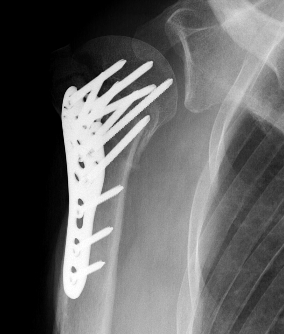

Apply plate

- lateral to biceps with single cortical screw in oblique hole

- check fluoroscopy - avoid having plate too high

- keep head out of varus to avoid cutout

- long inferomedial screws / kickstand screws

- locking screws

Plates

Synthes 3.5 mm LCP Proximal humeral plate surgical technique PDF

Long proximal humerus plates

Synthes 3.5 mm LCP Periarticular proximal humerus plate surgical technique PDF